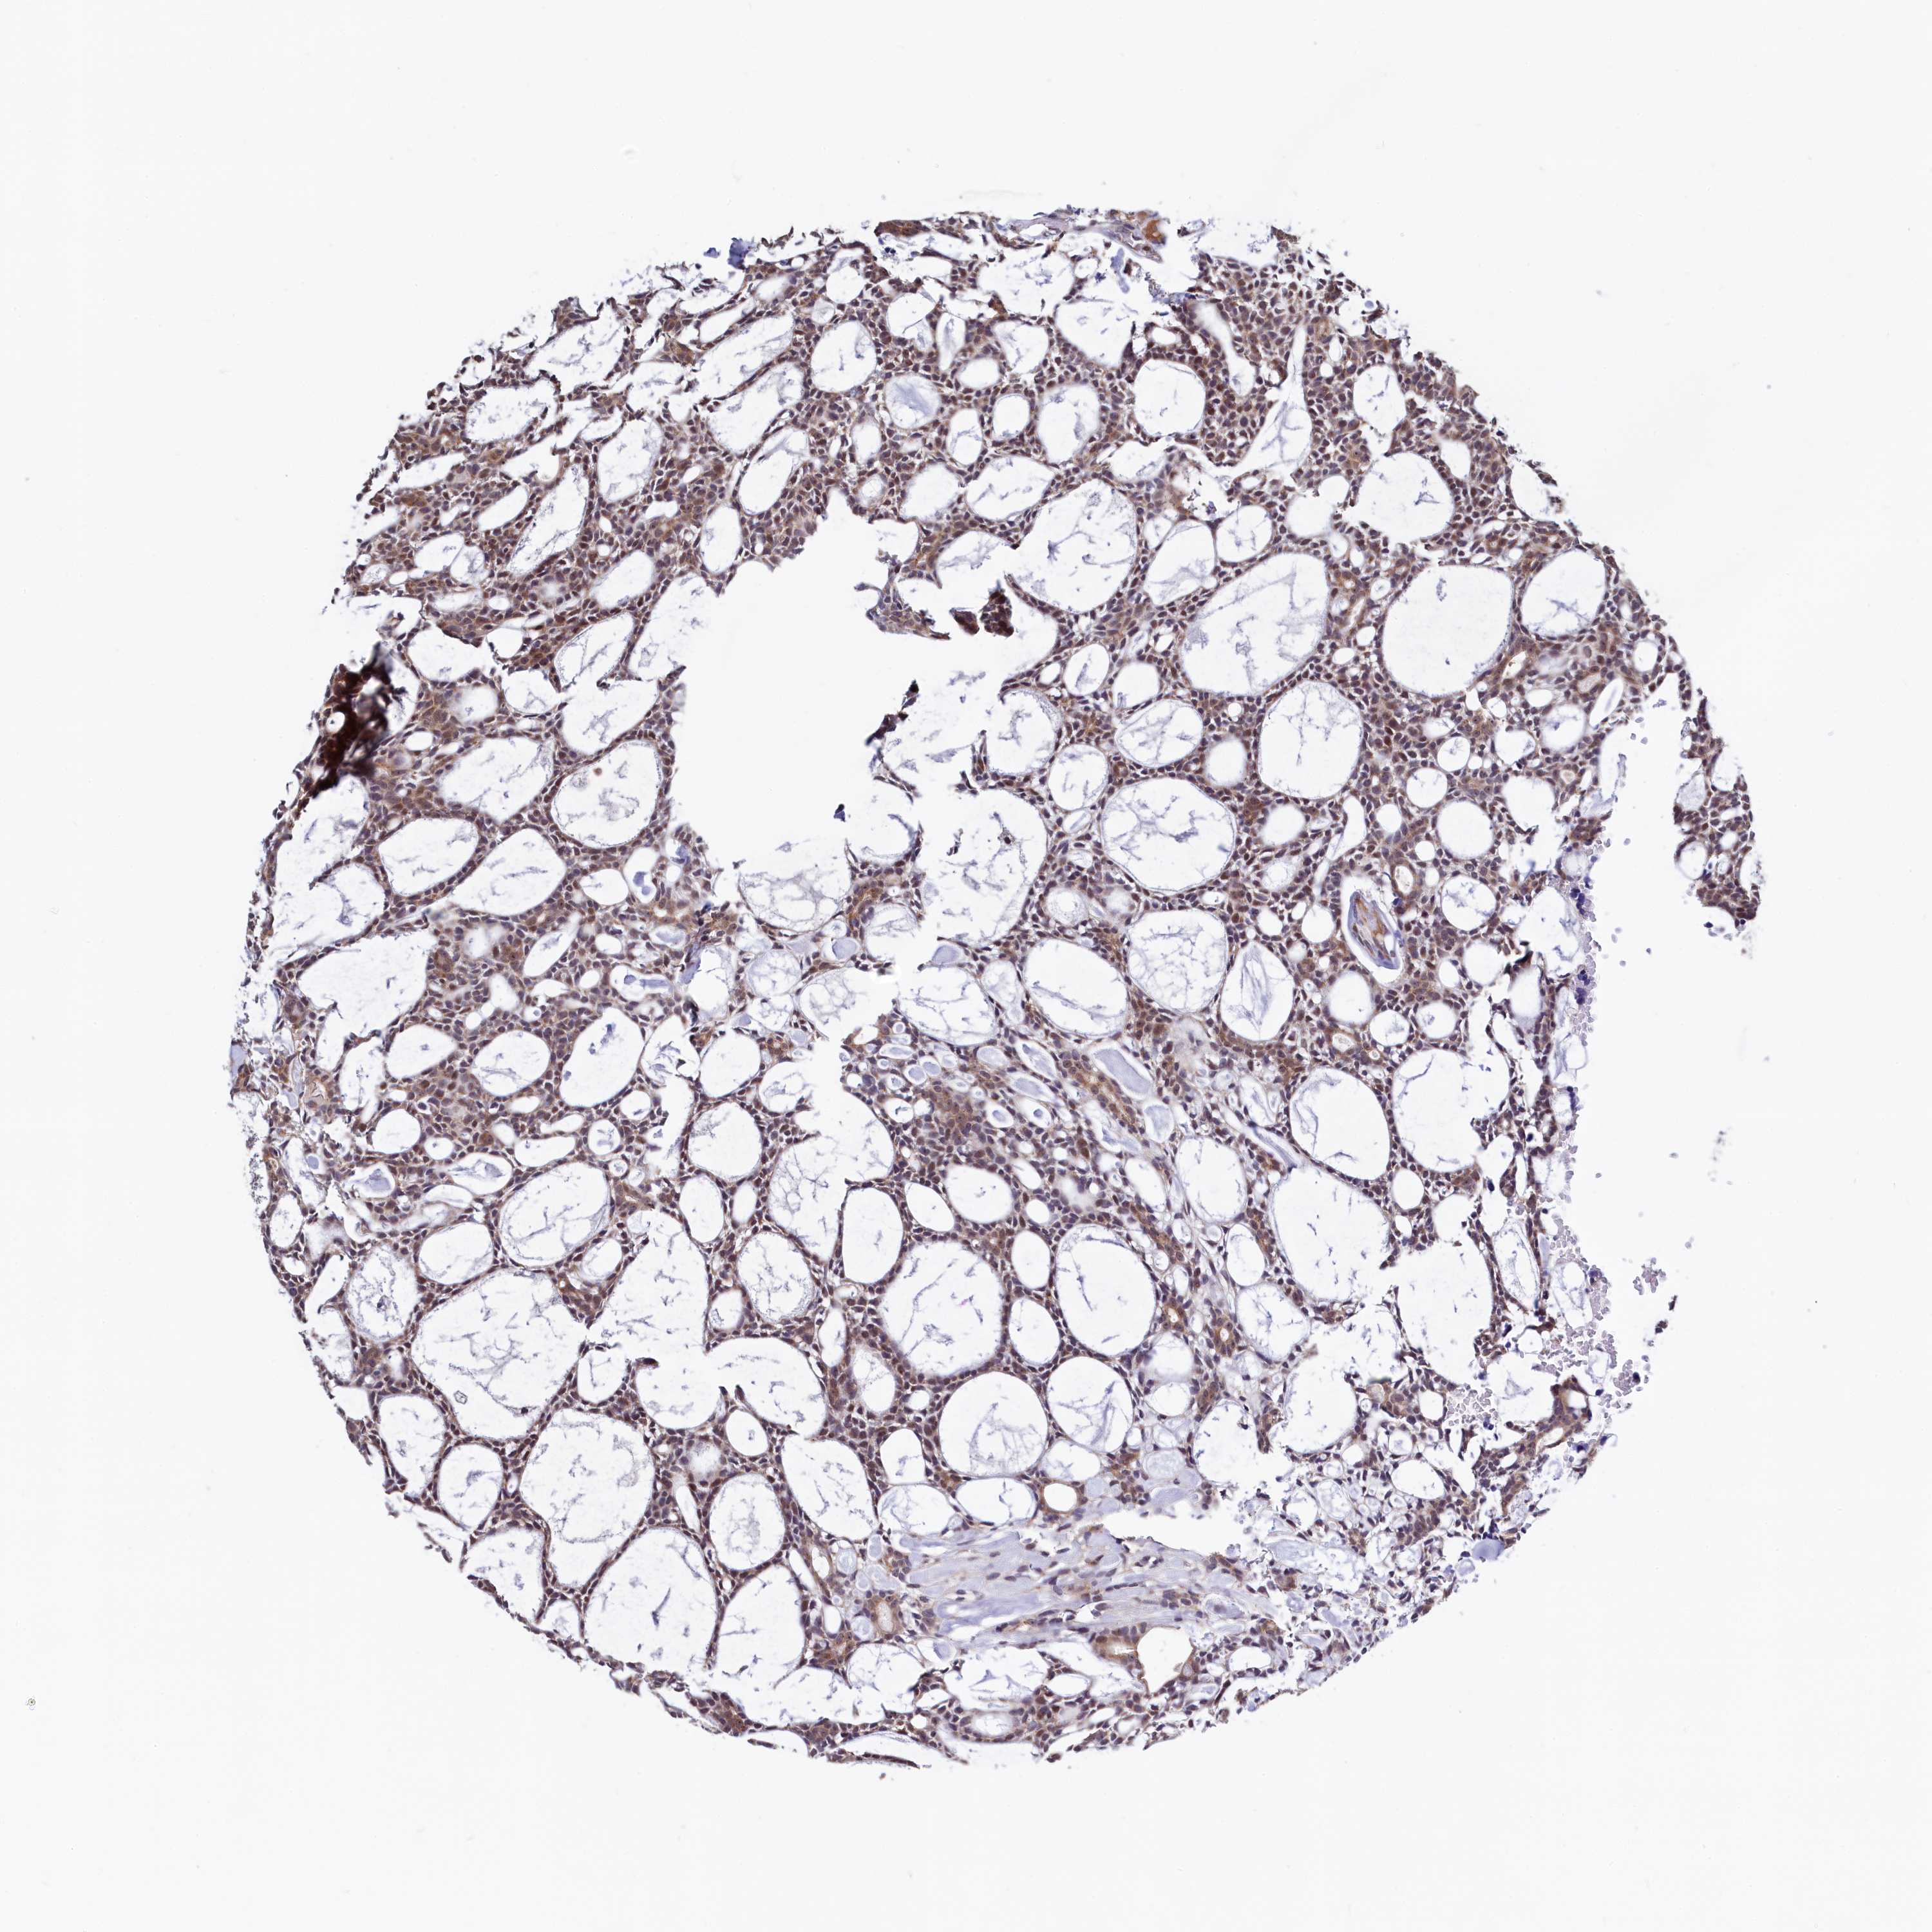

HEAD AND NECK CANCER - Protein expressioni

A mouse-over function shows sample information and annotation data. Click on an image to view it in a full screen mode. Samples can be filtered based on level of antibody staining by selecting one or several of the following categories: high, medium, low and not detected. The assay and annotation is described here.

Antibody stainingi

Antibody staining in the annotated cell types in the current human tissue is reported as not detected, low, medium, or high, based on conventional immunohistochemistry profiling in selected tissues. This score is based on the combination of the staining intensity and fraction of stained cells.

Each image is clickable and will lead to virtual microscopy that enables deeper exploration of all samples and also displays staining intensity scores, fraction scores and subcellular localization as well as patient and tissue information for each sample.

Antibody HPA040196

Staining

High

Medium

Low

Not detected

Intensity

Strong

Moderate

Weak

Negative

Quantity

>75%

75%-25%

<25%

None

Location

Nuclear

Cytoplasmic/membranous

Cytoplasmic/membranous,nuclear

Squamous cell carcinoma, NOS

Adenocarcinoma, NOS